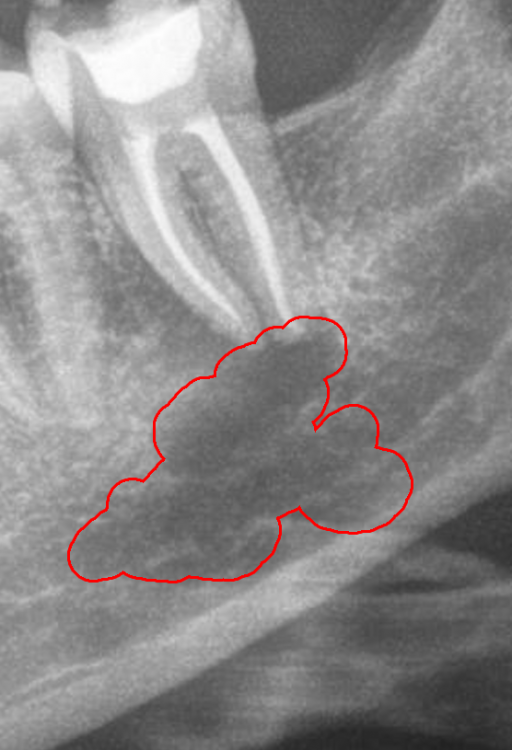

Начала ныть десна под депульпированной 10 лет назад нижней семеркой. Сделал панорамный снимок и под зубом штука похожая на кисту. Сходил на осмотр, на осмотре врач сказал что зуб слегка шатается, скорее всего у тебя под ним киста. Я показал снимок, врач сказал что да, это киста и посоветовал сделать КТ и сказал что нет проблем ее консервативно вылечить. (Распломбировать канал, положить лекарство и киста должна пойти на убыль). Но уже после НГ, сейчас все закрывается изза праздников.

Меня смущает форма кисты, она продолговатая, хотя по идее должна быть круглая. И темное пятно под кистой в челюсти (выделил красным). Или я непрвильно смотрю и киста это только то в зеленом кружочке?